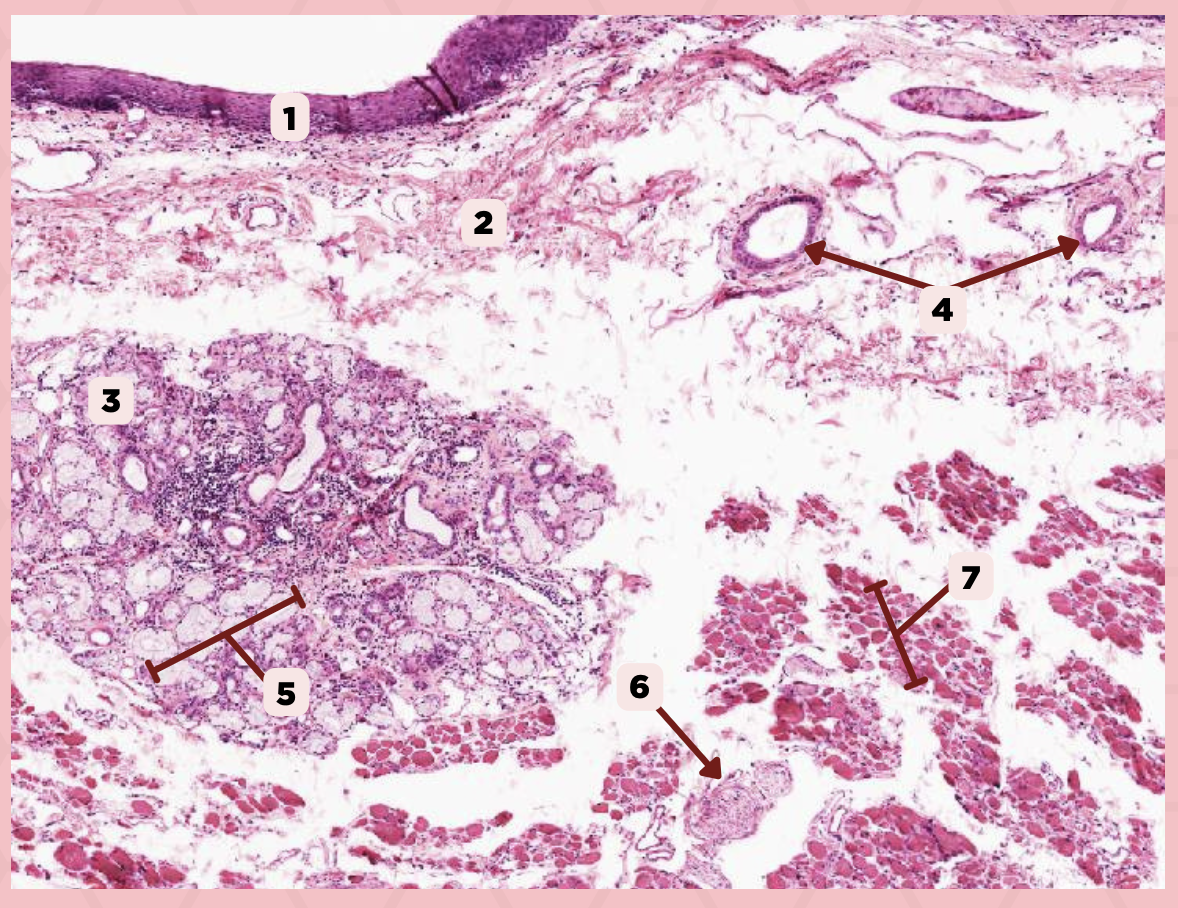

Lip

What is the specimen showed in the picture?

Epidermis

Identify the structure labeled as 1.

Dermis

Identify the structure labeled as 2.

Arrector Pilli Muscle

Identify the structure labeled as 3.

Hair Follicle

Identify the structure labeled as 4.

Sebaceous Glands

Identify the structure labeled as 5.

Lip

What specimen is showed in the picture?

Labial Glands (in the Mucosa)

Identify the structure labeled as 1.

Skeletal Muscle Cells

Identify the structure labeled as 2.

Lamina Propria

Identify the structure labeled as 3.

Mucosa

Identify the structure labeled as 4.

Lip

What specimen is showed in the picture?

Skeletal Muscle Fibers

Identify the structure labeled as 1.

Labial Glands

Identify the structure labeled as 2.

Cheek

Identify the specimen.

Mucosa

Identify the structure labeled as 1.

Lamina Propria

Identify the structure labeled as 2.

MALT

Identify the structure labeled as 3.

Blood Vessels

Identify the structure labeled as 4.

Buccal Glands

Identify the structure labeled as 5.

Nerve

Identify the structure labeled as 6.

Muscle Fascicles

Identify the structure labeled as 7.